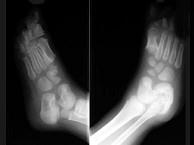

女,5岁,左踝疼痛,结合图像,最可能的诊断是?(?)A.创伤性关节炎B.退行性骨关节病C.神经性关节病D.风湿性关节炎E.痛风

问题 女,5岁,左踝疼痛,结合图像,最可能的诊断是?(?)

选项 A.创伤性关节炎 B.退行性骨关节病 C.神经性关节病 D.风湿性关节炎 E.痛风

答案 C